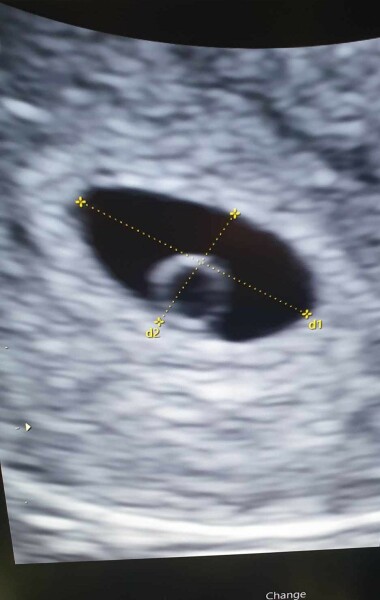

So i had my early ressurance scan today, The baby is in the right position and my date is correct 5 weeks 5 days today. We saw egg sac and gestation sac, and could also see that I ovulated from my left side wich confirms the pain I had 12/13 March when flo predicted my ovulation was wondering if I was feeling ovulation pain and seems I'm intuned with my body lol

Going back for my second scan 24th April where I will be 8 weeks to hopefully see fetal pole and heartbeat

@UnicornPrincessSarah congratulations, beautiful picture❤️ so happy for you xx

Thank you, hubby was like its real now he didn't full 100% belive the tests pmsl